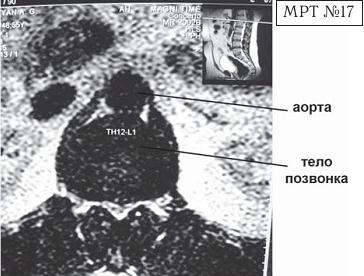

На МРТ № 17 наблюдается вентральная грыжа межпозвонкового диска в сегменте ThXII-LI с выраженными спаечными процессами на этом уровне, с вовлечением в данный процесс брюшной аорты В сагиттальной плоскости (вертикальный срез) грыжи межпозвонковых дисков разделяют на вентральные, дорсальные, краниальные и каудальные. МРТ № 18

Рисунок М°24. Зоны возможной локализации грыжи межпозвонкового диска в аксиальной плоскости Классификацию межпозвонковых грыж в сагиттальной плоскости мы рассмотрим ниже. А сейчас предоставляю вашему вниманию несколько наглядных примеров межпозвонковых грыж и их локализацию в аксиальной плоскости (из истории болезней пациентов). Вентральная локализация грыжи межпозвонкового диска как правило клинически ничем характерным не проявляется и определяется случайно (при обследованиях, связанных с другими заболеваниями позвоночника). Однако она не менее опасна, чем дорсальная грыжа межпозвонкового диска, особенно из-за близкого расположения аорты. Дело в том, что по анатомическому расположению брюшная часть аорты начинается на уровне XII грудного позвонка и, проходя по передней поверхности тел поясничных позвонков (немного левее срединной линии), продолжается практически до уровня середины тела IV поясничного позвонка. При вентральной грыже межпозвонкового диска значительных размеров в верхних сегментах поясничного отдела позвоночника могут возникать «конфликты» грыжи с аортой и соответственно спаечные процессы с вовлечением в них последней, что в свою очередь может привести к нарушению кровообращения в области малого таза и нижних конечностей. МРТ № 11 ![]() МРТ № 12